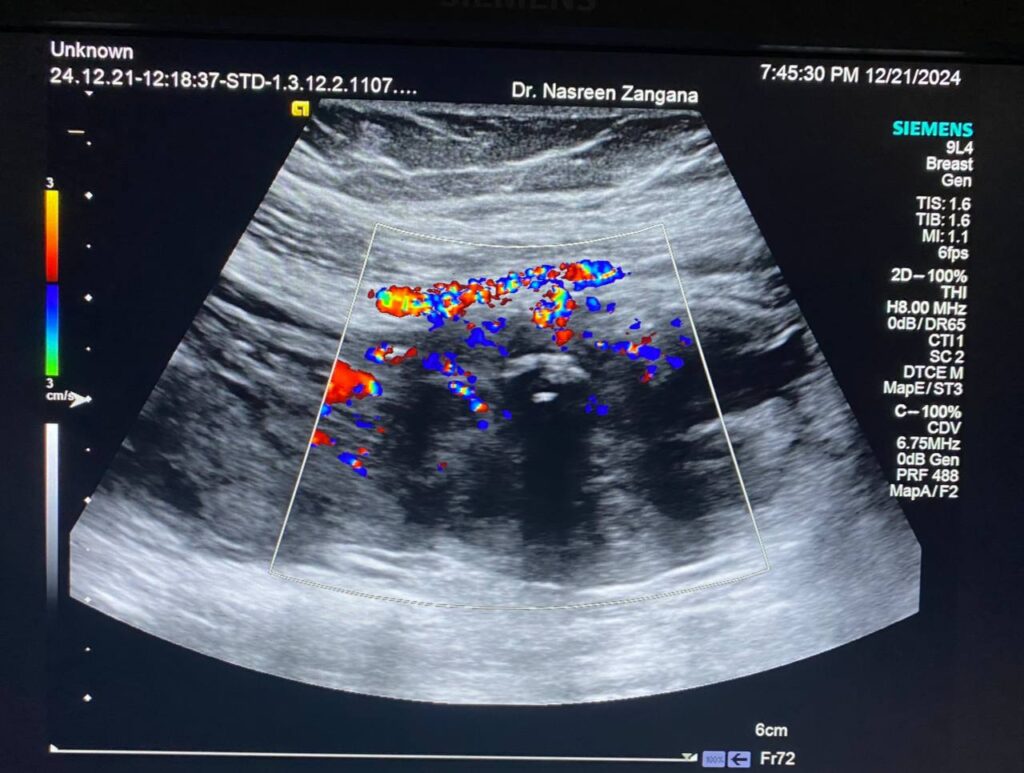

· Left ovary , normal in size , no dominate follicle , with presence of heterogenous vascular solid mass, contain calcification size about 44x30mm with indistinct margin, vascular on color doppler, score 3-4 located just the lateral to the left ovary , with invasion of the adjacent peritoneal & muscular layer ( left rectus abdominis muscle) , mostly suspicious mass , its invasion to the left ovary cannot be excluded , picture could be Desmoid tumor ? peritoneal tumor > , for further study please . no suspicious lymph node seen

- Evidence of 6 X 4 X 3cm multilocular mass in Lt lower abdomen, arises from Lt adnexa “attached to uterus and Lt ovary”, invades posterior aspect of Lt rectus muscle, in contact with Lt inferior epigastric artery, also in contact with loop of small intestine with no frank invasion, this mass has surrounding fat stranding, which makes it possible to be infection like tubo-ovarian abscess, although malignancy can not be excluded, lab studies and MRI is suggested for further evaluation please.